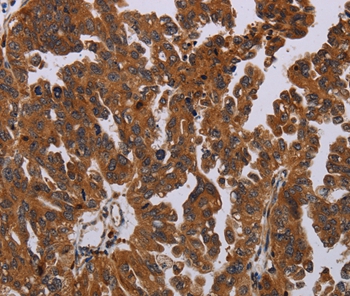

ApplicationsImmunoFluorescence, ELISA, ImmunoHistoChemistry, ImmunoHistoChemistry Frozen, ImmunoHistoChemistry Paraffin

- Applications SupplierELISA(ELISA=1:30-3000), IHC-P(IHC-P=1:100-1:200), IHC-F(IHC-F=1:100-1:200), IF(IF=1:100-1:200)